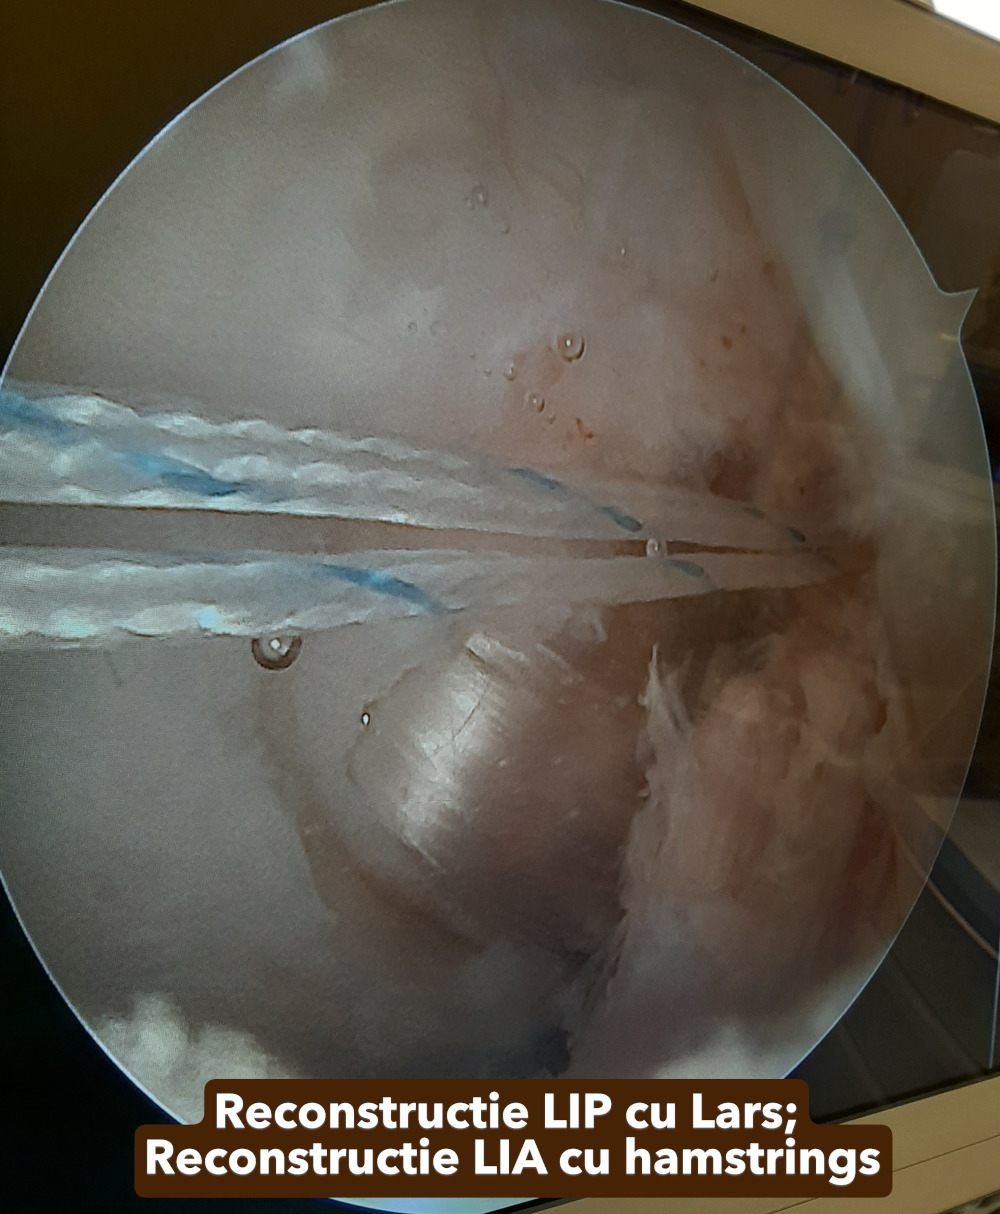

Galerie imagini cu leziuni ligamentare si meniscale tratate de dr. Chitea Claudiu-Daniel